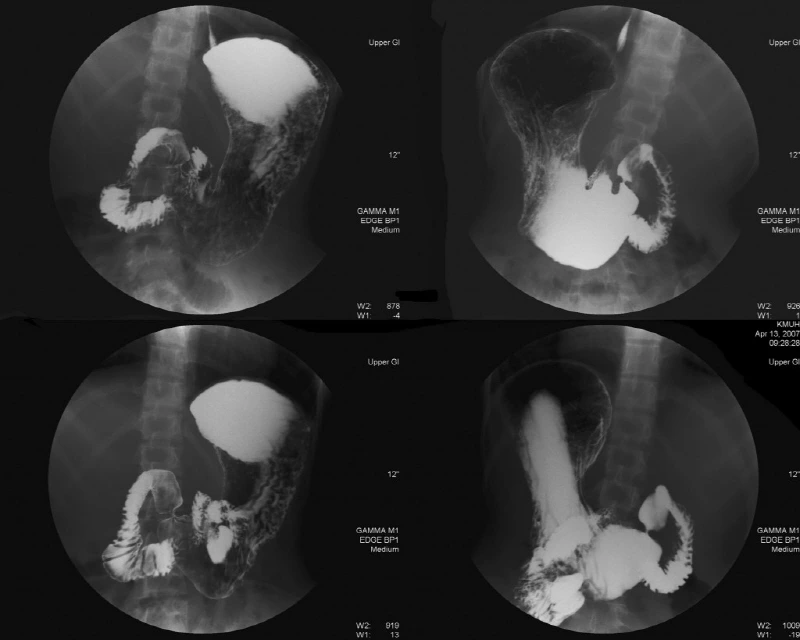

기쁜 마음으로 달려간 위조영술실 앞에는 대기자가 한 명도 없었다. 심지어 방사선사님도 안계셔서 5분 정도를 기다려야 했는데, 검사실로 들어가자 방사선사는 바륨 조영액을 나에게 건넸다. 꾸덕꾸덕한 하얀색 페인트같은 조영액을 꾸역꾸역 마시고 나니 정면의 엑스레이 모니터상에 용액이 흘러 내려가는 것이 보였다. 오... 신기해... 내 식도와 위장이 저렇게 생겼구나...

퍼온 사진

몇 장의 사진을 찍은 뒤 이번에는 기포제와 용액을 함께 먹으란다. 그 뿐만 아니라 트림이나 기침이 나도 절대 하면 안되고 최대한 버텨야 한다는 미션까지 주어졌다. 또다시 그 허연 페인트를 마시고 나니 용액이 꽤 아래까지 내려가 장까지 흘러간 것이 보였다. 방사선사는 이번에는 조영액이 위장에 골고루 발라질 수 있도록 엑스레이 판에 누워서 오른쪽으로 2바퀴만 구르란다. 생각지도 못한 요구에 당황했지만 골고루~ 골고루~ 발라질 수 있도록 최대한 정성스럽게 오른쪽으로 2바퀴를 굴렀다.